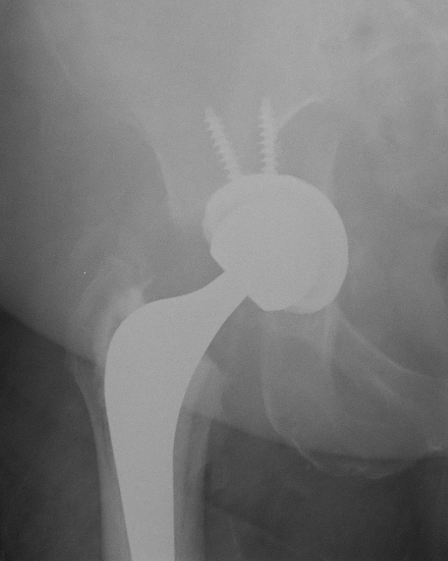

Callous from occult intra-operative acetabular fracture

Undisplaced fracture + stable cup

Acetabular screws

Touch weight bear for period